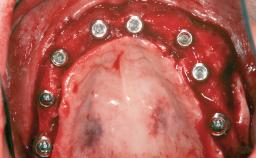

Ridge Preservation and Implant Placement for a Fixed Dental Prosthesis After a Car Accident

# of Teeth 6

# of Implants 4

Type of Implants One-Piece|Reduced-Diameter

Bone Augmentation Horizontal|Simultaneous|Sinus Floor Elevation|Staged

Defining Characteristics More than three missing teeth to be replaced with an implant-borne prosthesis or prostheses